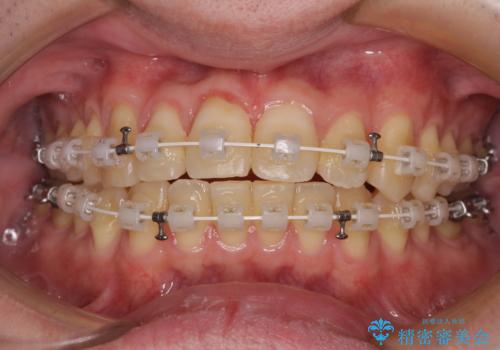

- 矯正装置

- 審美装置

- 前歯のデコボコとクロスバイトを気にして来院された患者様です。

インビザラインでもワイヤー装置でも矯正治療は可能でしたが、煩わしい自己管理なしに短期間で治療を行いたいとのことで、目立たないワイヤー装置にて治療を行うこととしました。